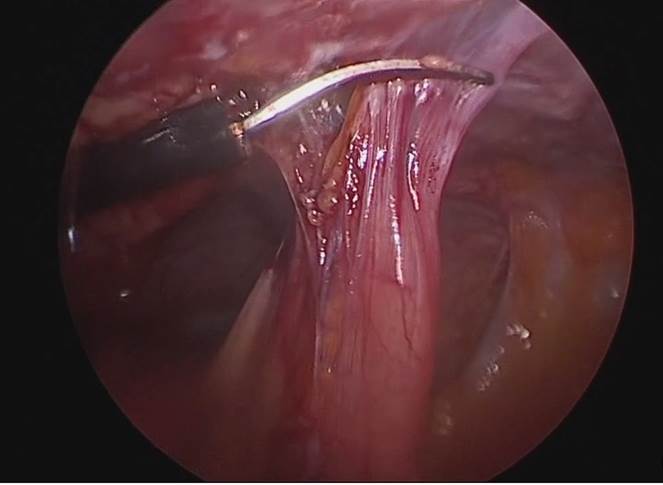

6. Reparación de la fístula. Se diseca la pared posterior de la vejiga de la pared anterior de la vagina con disección roma o cortante. Se procede a realizar fistulectomía circunferencial con corte frío (Fig. 8), se completa disección y separación de pared vaginal de la vesical (Fig. 9).